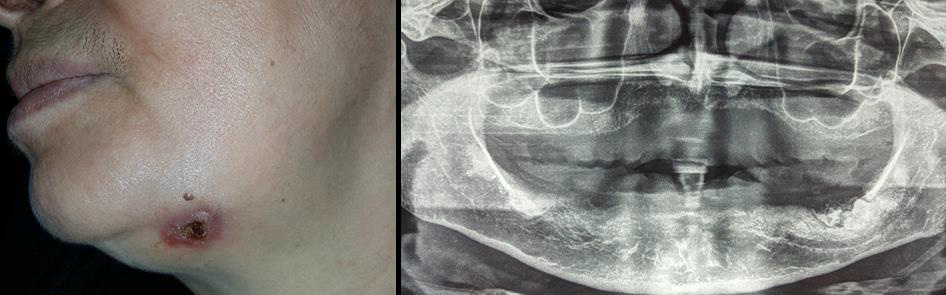

Another misdiagnosed case related to a wrong approach of clinical examination: the patient consulted a dentist because of appearance of an ulcerative cutaneous sinus tract in her left submandibular area (Figure 4A). Ignoring to make a correct diagnosis of her condition, he sent her to a dermatologist since the lesion was in her skin. The dermatologist prescribed only topic medication without any good improvement. The patient was referred to our department. Orthopantomogram showed a presence of radiopaque lesion in the left molar mandibular region (Figure 4B). Biopsy of the lesion had concluded a suppurative osteomyelitis, which was the principal etiology of the cutaneous sinus tract.

Figure 4: (A) extraoral view submandibular cutaneous sinus tract.

(B) Orthopantomogram showed a left mandibular radiopaque lesion.